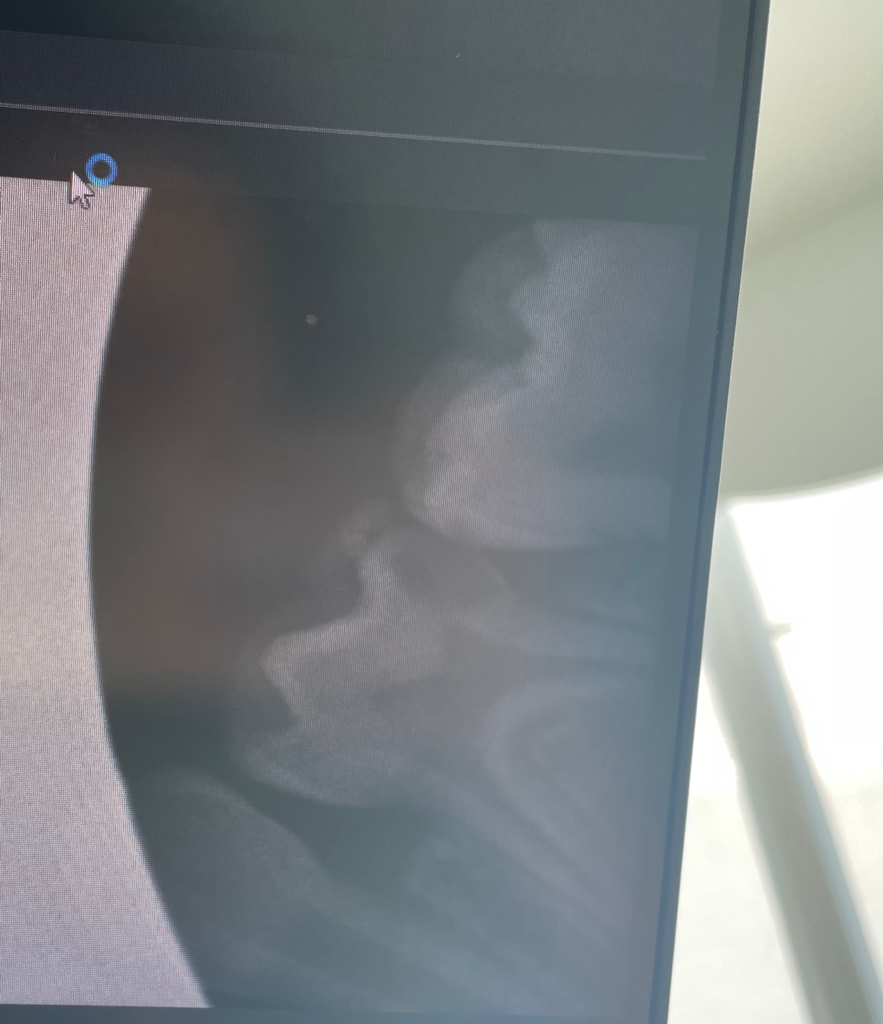

혹시 이거 신경치료 해야하는걸까요?? ㅜㅜ 우식증이 있다고는 하셨고 검진 마치고 나오기는 했는데 ㅠㅠ

• 1번 째 사진

아이치아에 충치가 상당히 많이 진행된거 같습니다. 신경치료를 하고 은니를 씌워야될것같습니다.

치아를 삭제해봐야 알지만 신경치료를 해야할 가능성이 높아보이고 옆의 치아도 치료를 해야 합니다.

1. 주어진 방사선 사진상으로는 꽤 충치가 깊으며 충치를 제거하다보면 신경이 노출되어 신경치료 내지는 부분신경치료가 필요할 수 있겠습니다.

2. 아무래도 치아 사이 충치 (인접면 충치)이기 때문에 두 치아가 같이 영향을 받았습니다. 그 옆 치아는 레진이나 GI 등의 수복 치료가 필요할 것 같습니다.

3. 유치라 하더라도 아직까지 영구치로 교환되기까지 남아있고 저렇게 충치가 큰 경우 치아가 나중에 깨져나가거나 하면 굉장히 아픈 상태가 되고 영구치에도 충치 감염 등의 영향을 미치게 되므로 조치를 취해주는 게 좋습니다.